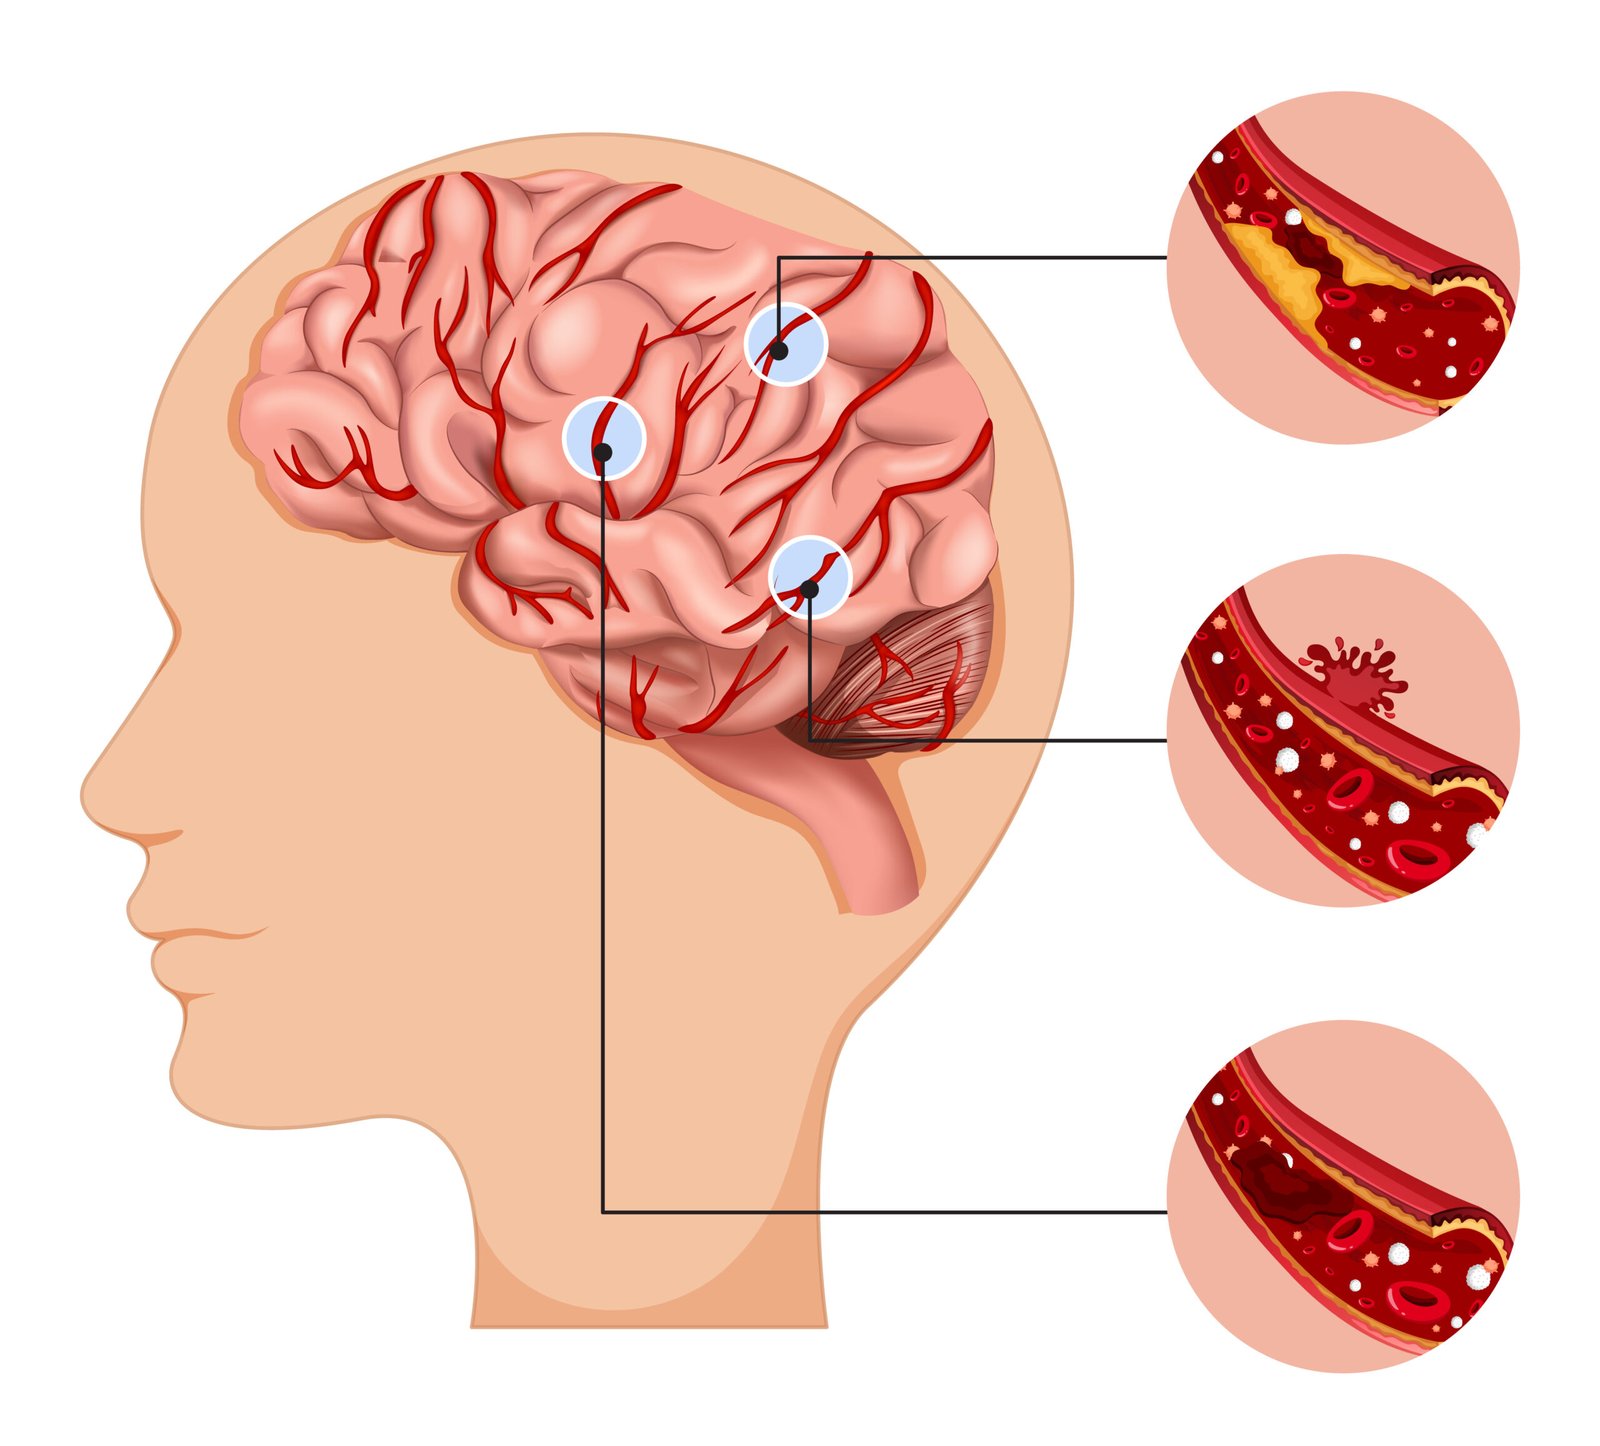

Vascular screenings are non-invasive medical tests used to assess the health of blood vessels and detect any abnormalities or blockages. These screenings are essential for identifying conditions such as:

Carotid Artery Ultrasound. A carotid artery ultrasound is a painless, non-invasive test that uses sound waves to create images of the carotid arteries in the neck. These arteries supply blood to the brain, and narrowing of these vessels can increase the risk of stroke. During the test, a small transducer is placed on the neck to measure the flow of blood and detect any blockages or abnormalities.

- Improved outcomes: Early detection allows for more treatment options and better management of vascular diseases. It can significantly reduce the risk of complications such as stroke, heart attack, or limb amputation.